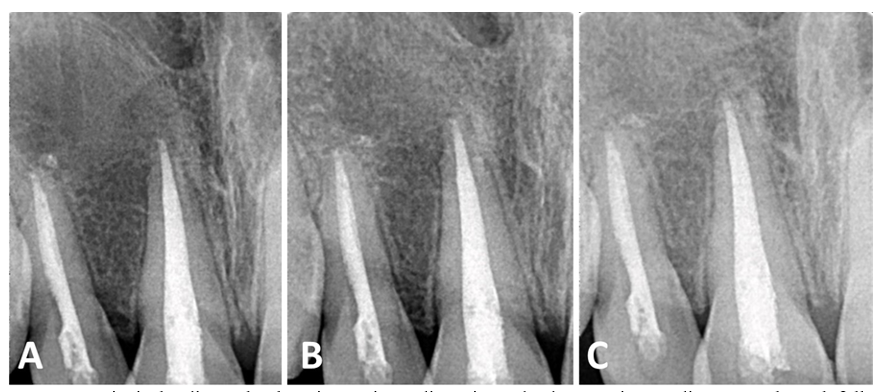

The patient did not report any painful symptoms during the 3-month rest treatment or at other follow-up visits. The case was clinically asymptomatic as all signs and symptoms had disappeared completely, and the gingiva appeared normal on follow‐up recall (Figure 3). Periapical radiographs show signs of healing of the periapical lesion, increasing radiopacity, and decreasing root divergence through follow‐up recall at 6, 12, and 18 months (Figure 4).

Figure 4 Periapical radiographs show increasing radiopacity and a decrease in root divergence through follow-ups at 6 (A), 12 (B), and 18 (C) months.